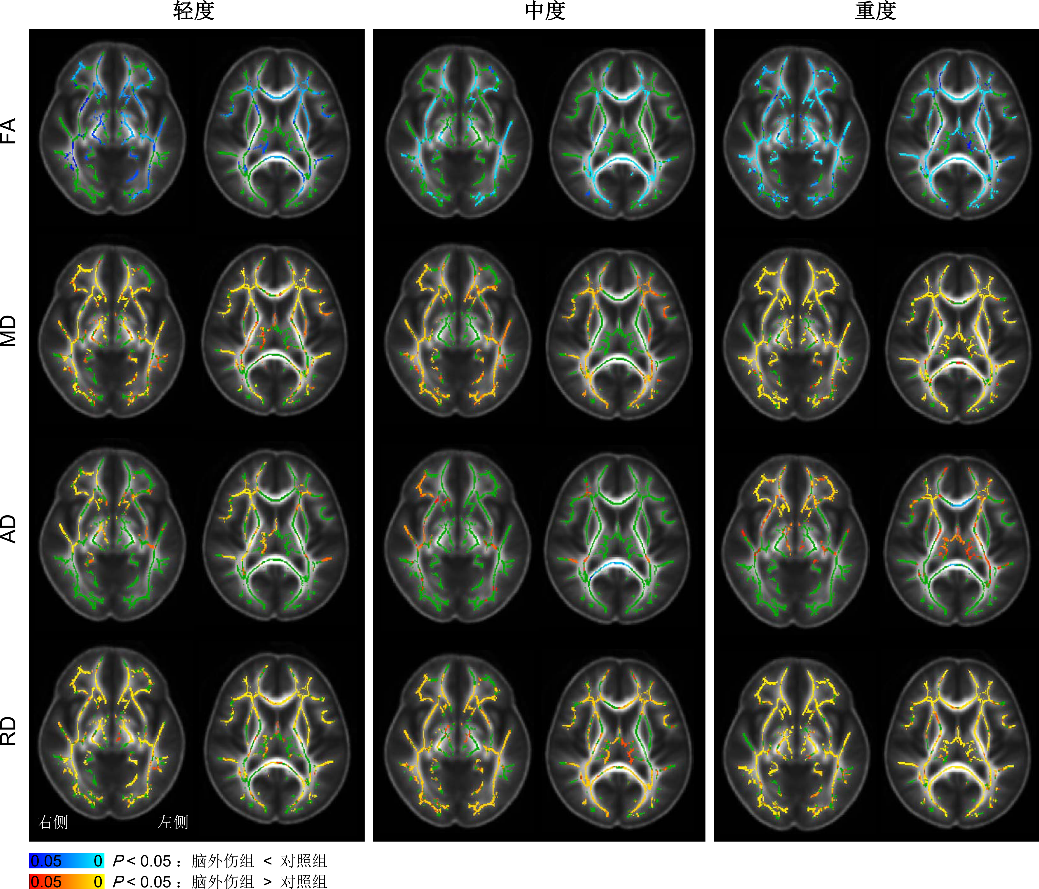

TBSS显示,与对照组相比,重度较轻、中度组损伤更严重,AD轻度组升高,而中、重度组胼胝体膝部及压部降低(见图1)。

图1 DTI参量TBSS分析

所测量区域中各参量均存在组间差异的区域包括:胼胝体膝部(genu of corpus callosum,GCC)、左侧下额枕束(left inferior fronto-occipital fasciculus,IFOF-L)、右侧下额枕束(right IFOF,IFOF-R)、右侧下纵束(right inferior longitudinal fasciculus,ILF-R)、左侧钩束(left uncinate fasciculus,UF-L)、右侧钩束(right UF,UF-R)。与对照组比较,TBI患者FA降低, MD、AD、RD升高(见图2、表2)。